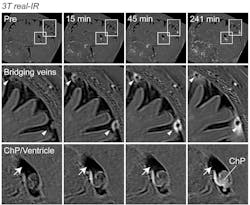

Using MRI, the researchers scanned the brains of a group of healthy volunteers who had received injections of gadobutrol, a magnetic dye used to visualize disruptions in the blood brain barrier or other kinds of blood vessel damage. Large veins are known to pass through the arachnoid barrier carrying blood away from the brain, and these were clearly observed on the MRI scans. As the scan progressed, a ring of dye appeared around those large veins that slowly spread out over time, suggesting that fluid could make its way through the space around those large veins where they pass through the arachnoid barrier on their way into the dura.

Together, the labs found a “cuff” of cells that surround blood vessels as they pass through the arachnoid space. These areas, which they called arachnoid cuff exit (ACE) points, appear to act as areas where fluid, molecules, and even some cells can pass from the brain into the dura and vice versa, without allowing complete mixing of the two fluids. In some disorders like Alzheimer’s disease, impaired waste clearance can cause disease-causing proteins to build up.